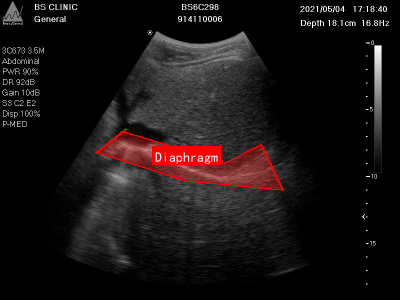

上图展示了一张典型的膈肌超声影像图,图像中红色框清晰标注了膈肌位置。膈肌在超声图像中表现为一条连续、略呈弧形的强回声带,位于肝脏或脾脏等腹腔器官与胸腔的分界处。通过分析膈肌的形态、位置及回声特征,可以评估膈肌完整性、厚度、活动度等指标,对诊断膈肌病变(如膈疝、膈肌麻痹)具有重要价值。

本数据集为Diaphragm数据集v7版本,采用CC BY 4.0许可协议,由qunshankj平台用户提供并导出。数据集包含315张腹部超声检查图像,所有图像均以YOLOv8格式标注,专注于膈肌(Diaphragm)的识别与定位。每张图像均为BS CLINIC机构的临床超声检查结果,设备型号为BS6C298,包含患者编号、检查时间、扫描深度(约16.8-18.1cm)、频率(16.8Hz)等临床参数。左侧参数栏详细记录了探头类型(如3D/7-3.5M、3CD73 SSM等)、检查部位(Abdominal腹部)、功率(PWR 90%)、动态范围(DR 92dB)、增益(Gain 100-108)、滤波设置(LB 0.2/C2 E2、G8 C2 E2等)及显示模式(Disp 100%、P-MED)等技术参数。图像主体呈现典型的腹部横断面超声灰度影像,清晰显示腹腔内不同组织的回声差异,包括低回声区和高回声结构。膈肌在图像中表现为弧形高回声带,通过红色多边形轮廓线精确标注,明确标识这一区分胸腔与腹腔的重要解剖结构。右侧刻度标尺用于测量深度,整体图像质量良好,细节可辨,为临床诊断提供膈肌位置、形态及周围组织关系的可靠参考。数据集未应用任何图像增强技术,保持了原始临床数据的真实性,适用于膈肌超声影像的自动检测算法研究与模型训练。